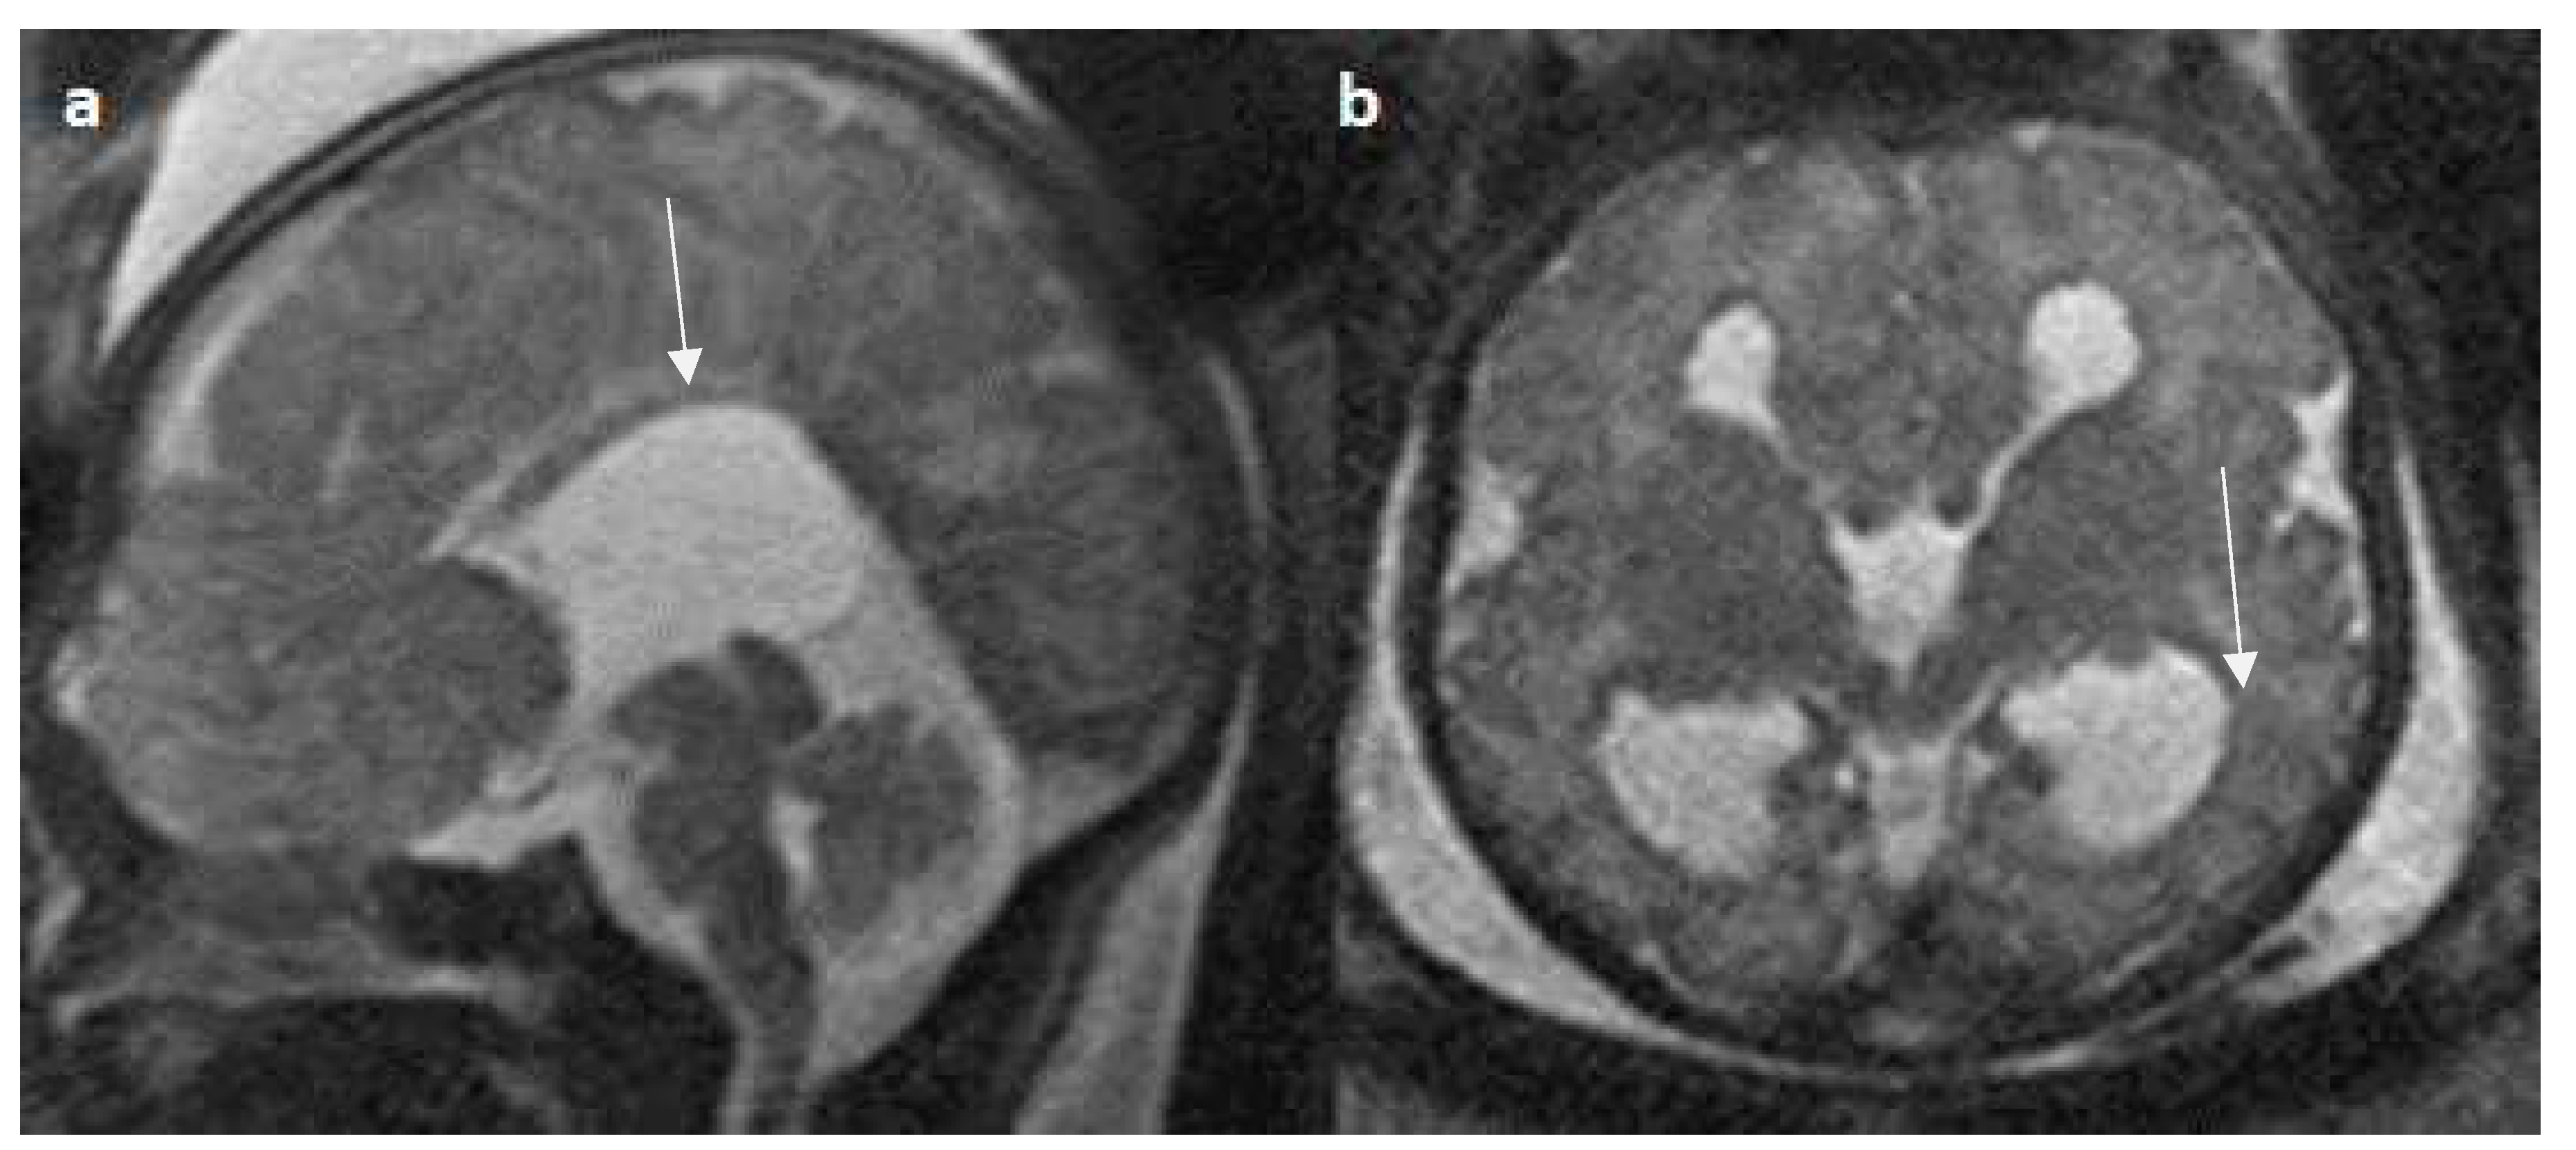

- Manor C, Rangasami R, Suresh I, Suresh S. Magnetic Resonance Imaging Findings in Fetal Corpus Callosal Developmental Abnormalities: A Pictorial Essay. J Pediatr Neurosci. 2020 Oct-Dec;15(4):352-357. [CrossRef]

- Hyun Yoo J, Hunter J. Imaging spectrum of pediatric corpus callosal pathology: a pictorial review. J Neuroimaging. 2013 Apr;23(2):281-95. [CrossRef]